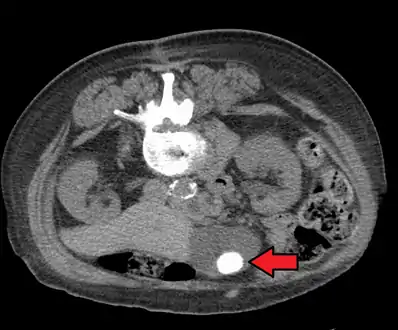

Diagnosis is typically confirmed by abdominal ultrasound. Other imaging techniques used are ERCP and MRCP. Gallstone complications may be detected on blood tests.[2]